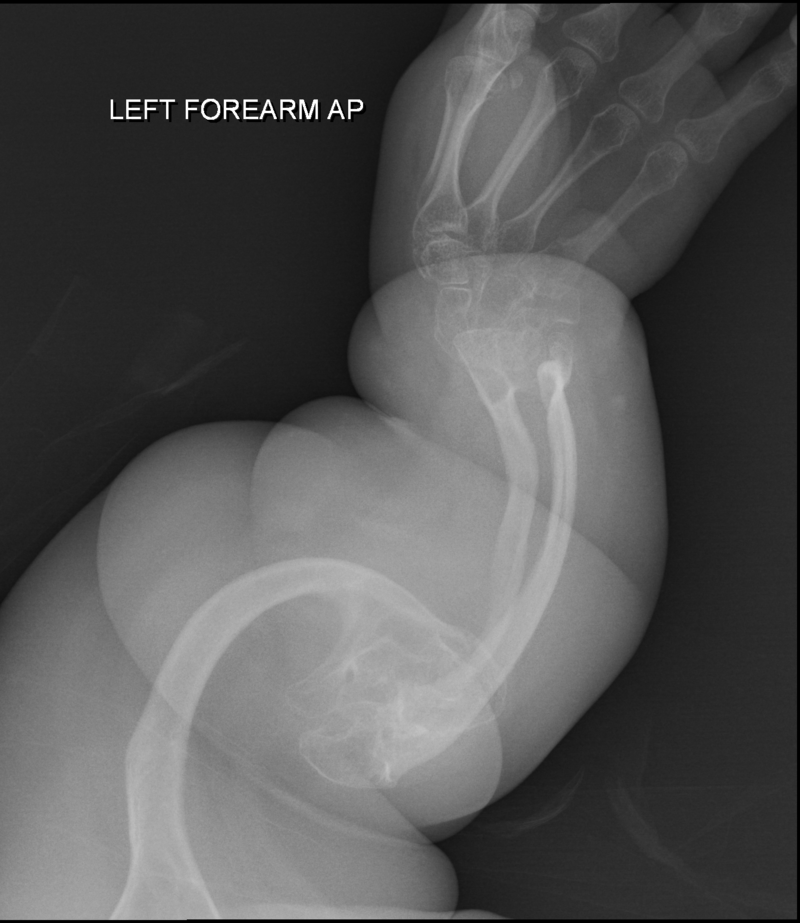

Osteogenesis Imperfecta (OI)

Osteogenesis imperfecta (OI) is a congenital bone resorption disease that results in structurally weak bone.

Osteogenesis imperfecta (OI) is caused by an autosomal dominant defect in collagen type I synthesis.

Clinical symptoms of osteogenesis imperfecta (OI) include:

- Blue sclera

- Hearing loss

- Multiple fractures of the bone

Note that the middle ear bones are also prone to fracture in osteogenesis imperfecta (OI).